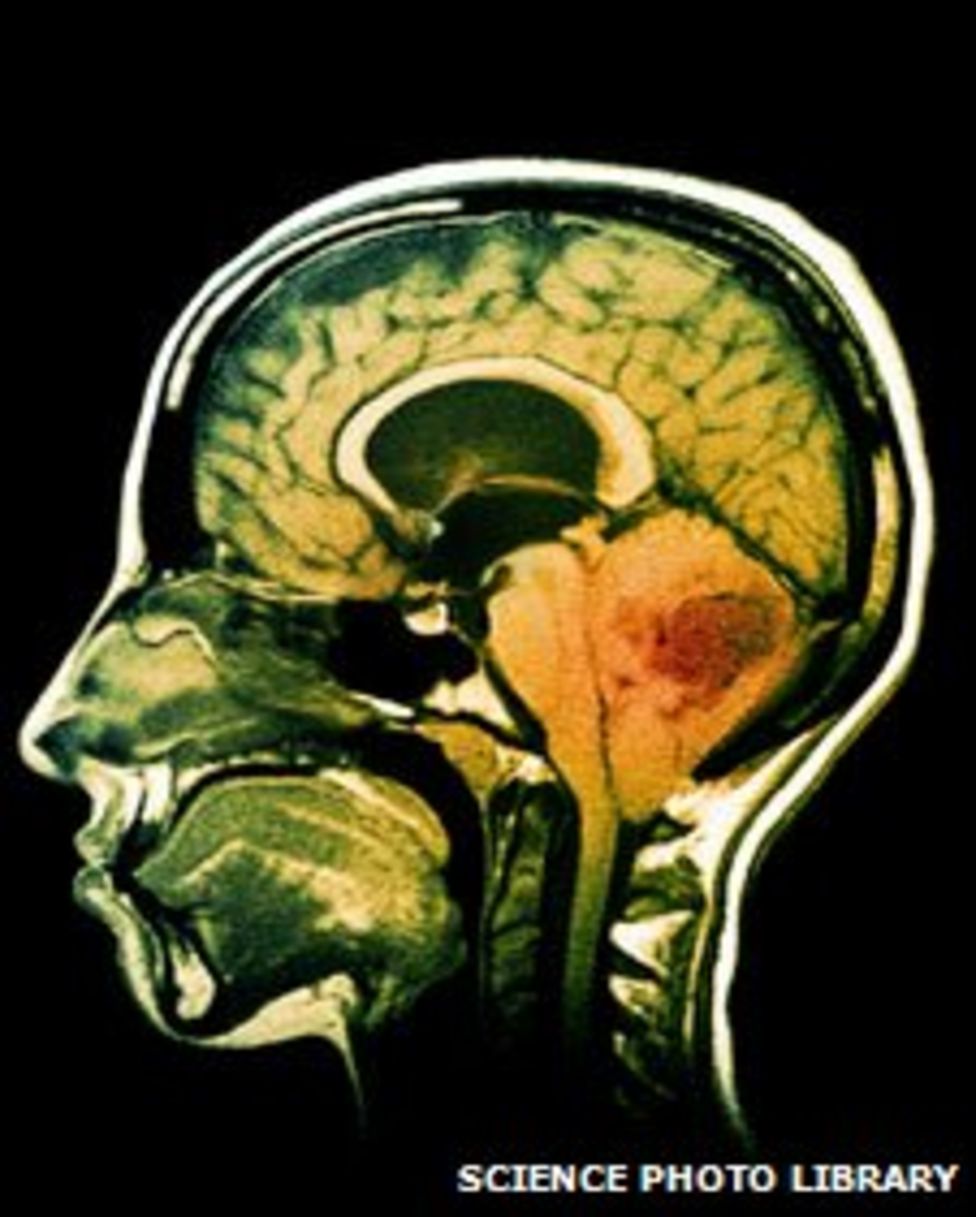

Blood Test For Brain Cancer . Do brain tumors show up in routine blood work? Brain cancers include primary brain tumours, which start in the brain and almost never spread to other parts of the body,. This test uses mri to measure the amount of blood in different parts of the brain tumor. A neurological and eye exam, lumbar puncture and blood tests may be used. The technique has been shown to be sensitive at detecting the. A brain tumor is diagnosed with brain mri or brain ct scan, with contrast fluid. Genetic mutations that promote the growth of the most common type of adult brain tumors can be accurately detected and. Liquid biopsy is a method for detecting cancer by looking for fragments of tumor dna that circulate in blood. The parts of the tumor that have a higher. No, blood tests cannot confirm or detect the presence of a brain tumor. Brain tumors originate from abnormal growth in brain.